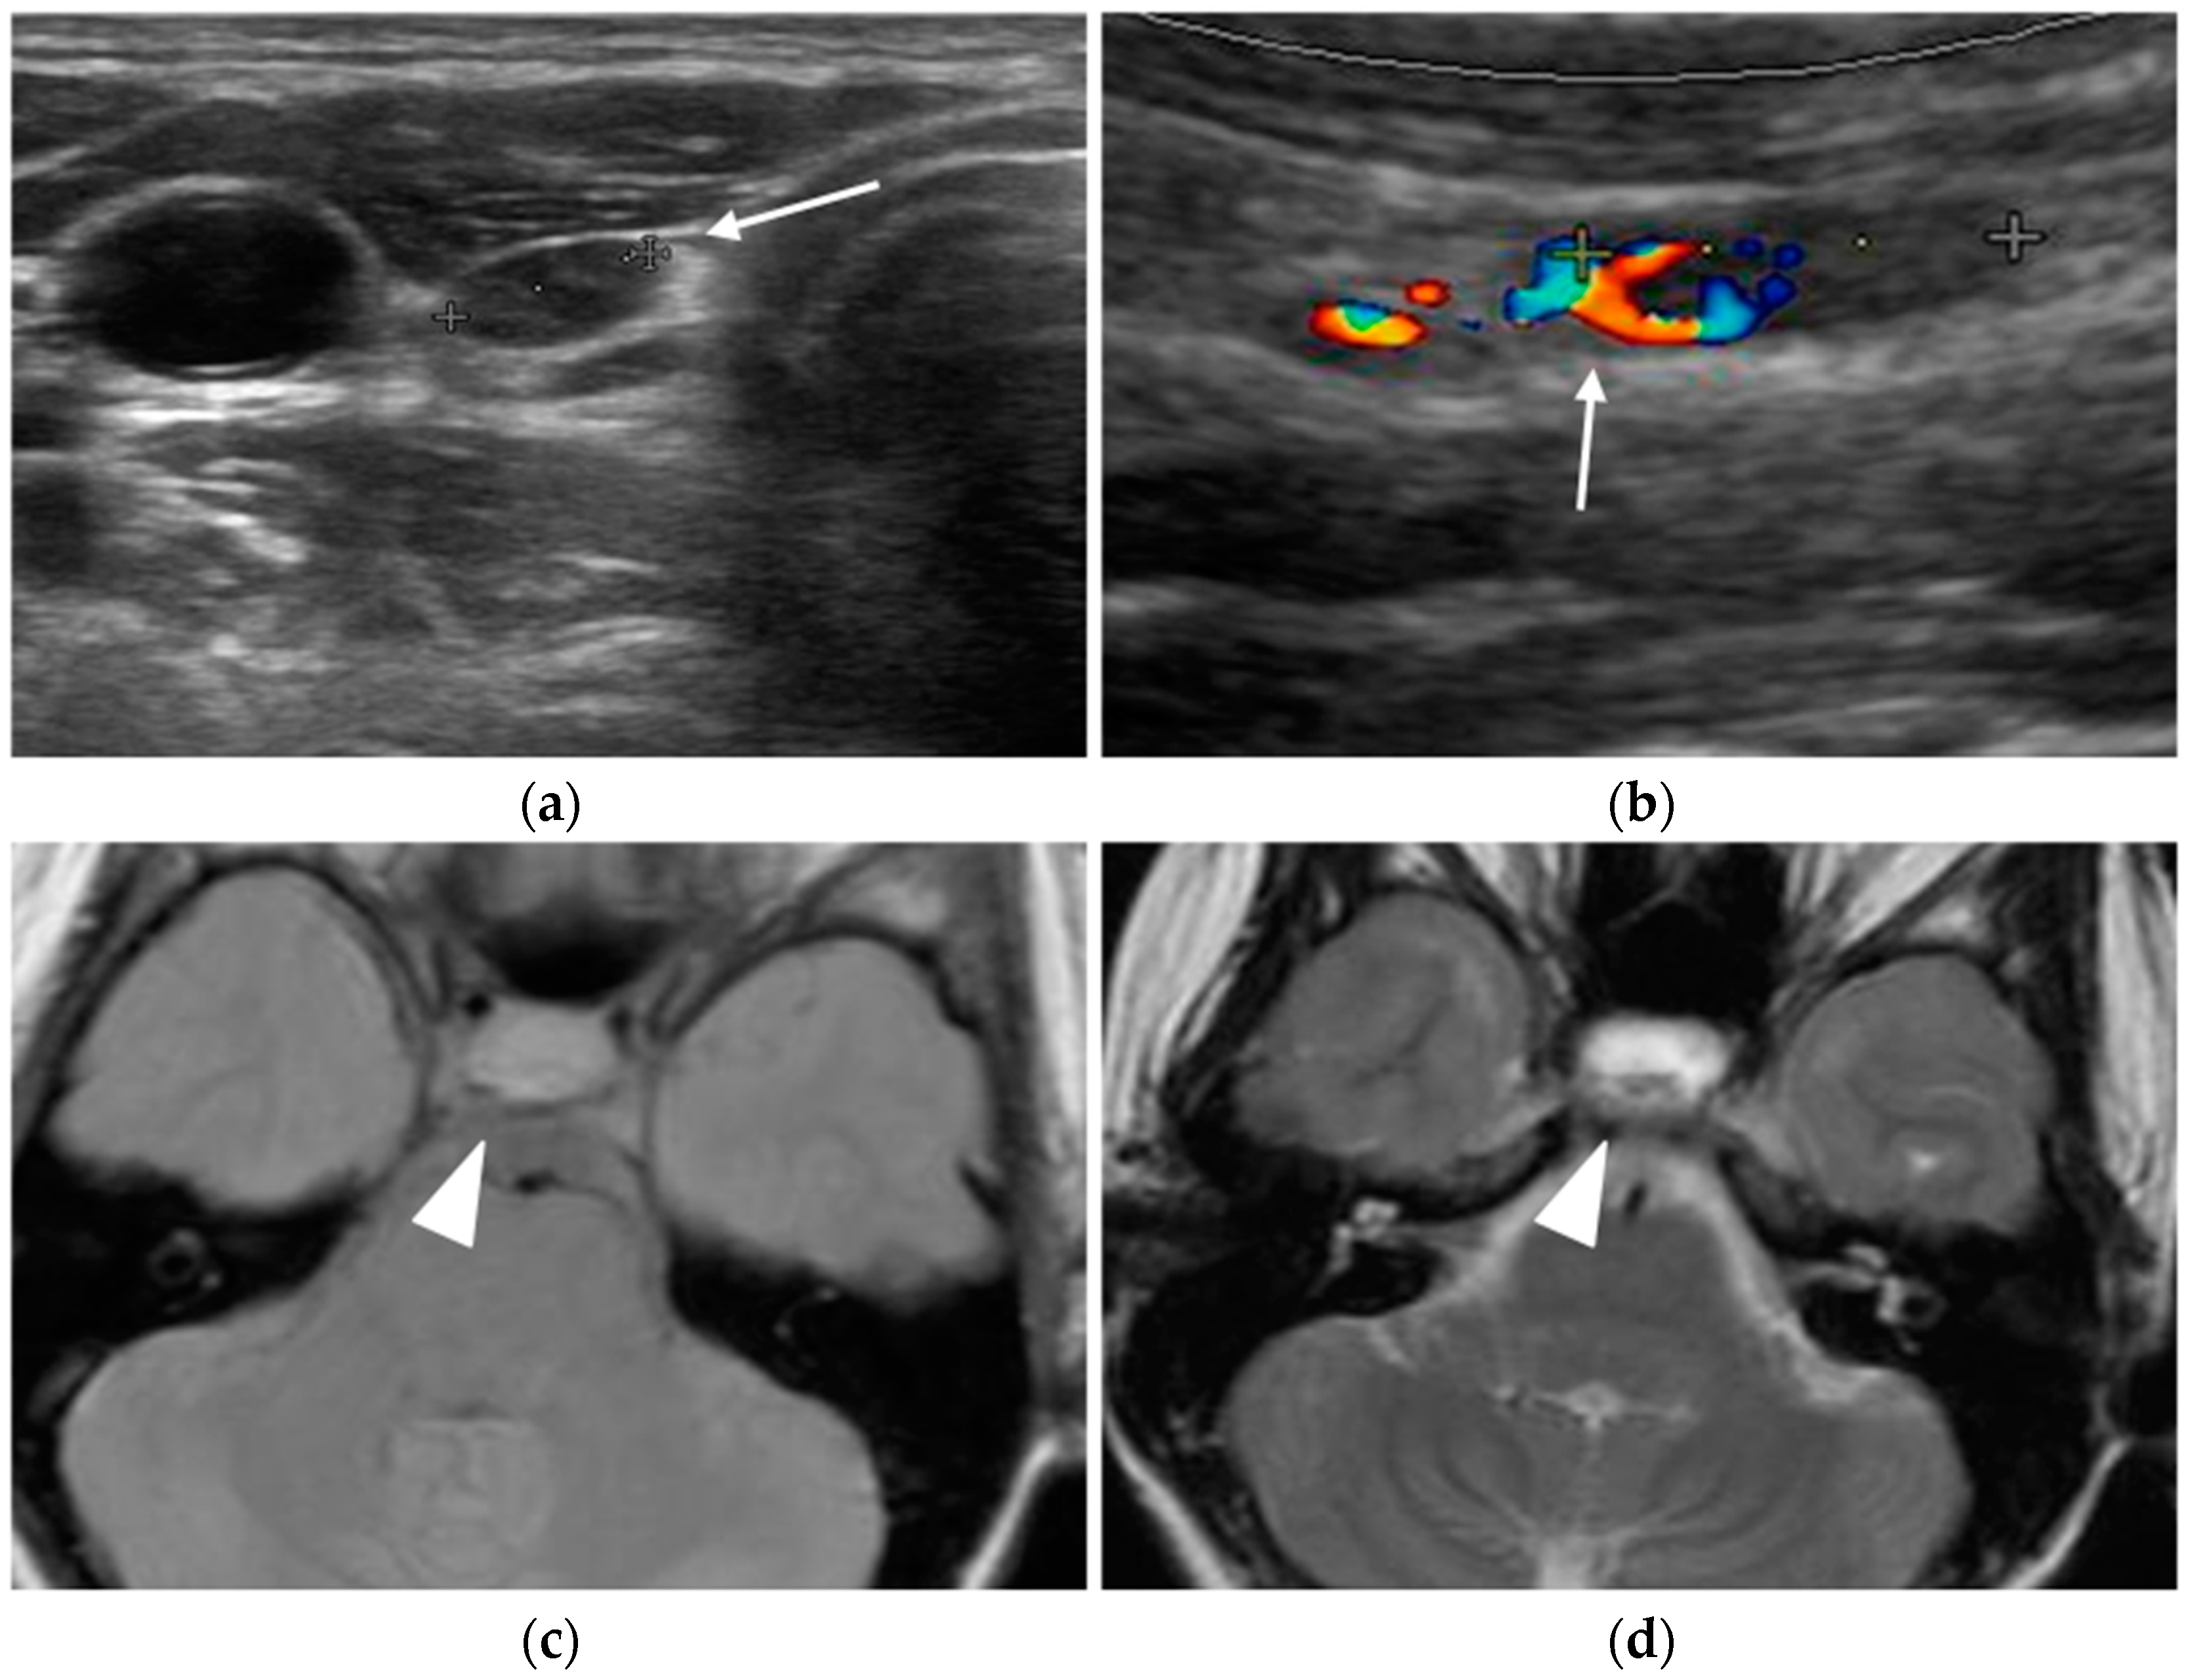

Ultrasound

- Rickes, S.; Sitzy, J.; Neye, H.; Ocran, K.W.; Wermke, W. High-resolution Ultrasound in Combination with Colour-Doppler Sonography for Preoperative Localization of Parathyroid Adenomas in Patients with Primary Hyperparathyroidism. Ultraschall Med. 2003, 24, 85–89. [Google Scholar] [CrossRef] [PubMed]

- Lane, M.J.; Desser, T.S.; Weigler, R.J.; Jeffrey, R.B., Jr. Use of color and power Doppler sonography to identify feeding arteries associated with parathyroid adenomas. Am. J. Roentgenol. 1998, 171, 819–823. [Google Scholar] [CrossRef]

MRI